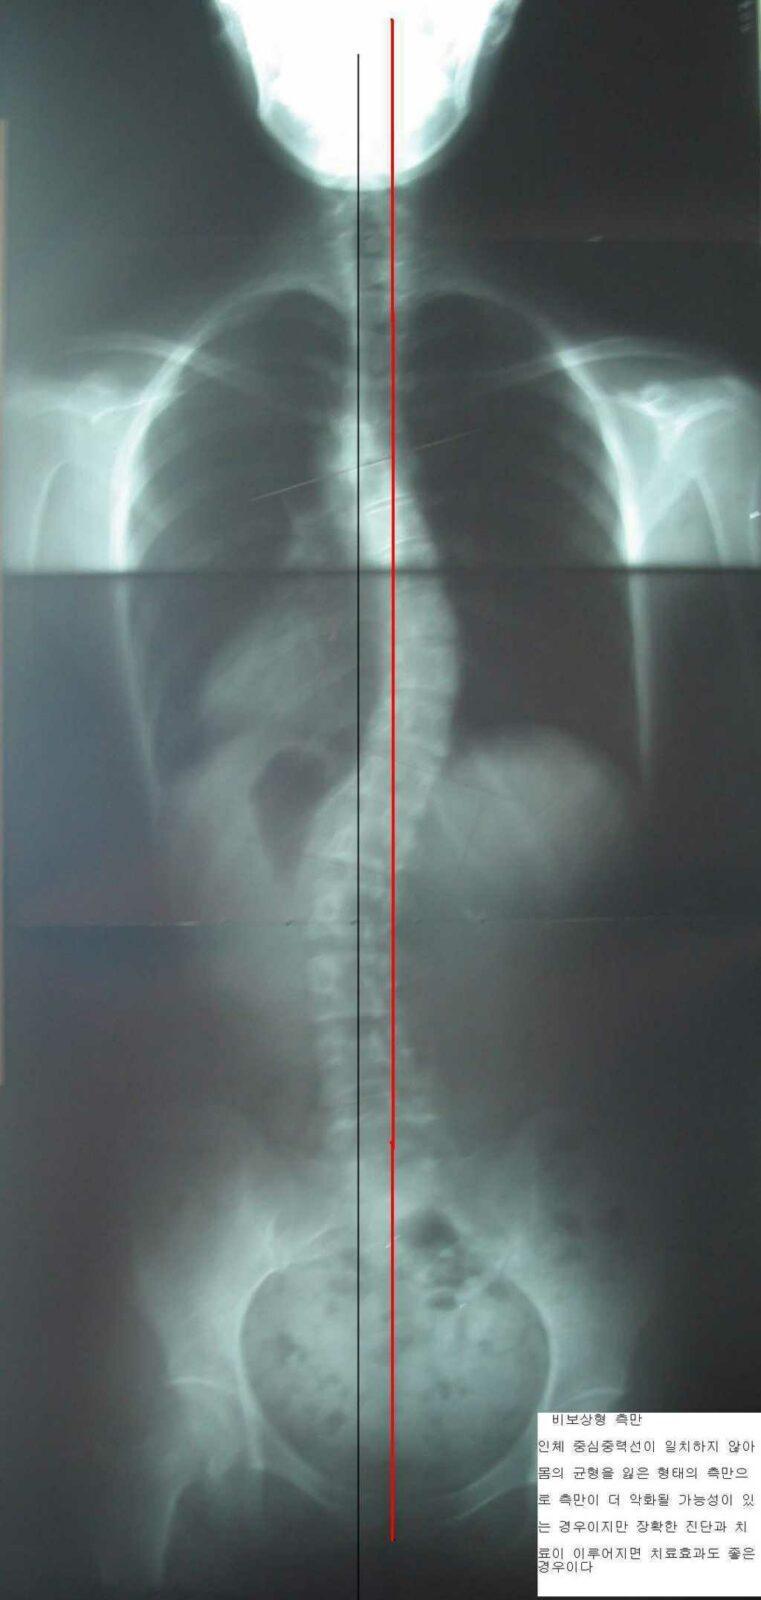

척추 측만증 치료 사례 2

분석 : 치료 전 13도의 측만에서 치료 후 7도의 측만으로 5도 정도의 호전을 보였습니다. .

치료 : 주 1회, 3개월간 치료 하였으며 호전 상태는 매우 양호합니다. 치료과정에서의 측만각도 호전을 보이고 있으나 현재 완전한 회복을 이룬 것은 아니므로 지속적인 치료가 필요합니다. 턱관절이 좋이 않아 학업에 지장이 많았으나 현재 턱관절도 좋아진 상태이며 추나요법과 매선요법을 겸하여 치료 하였습니다. 현재 과전만 치료 중 입니다.